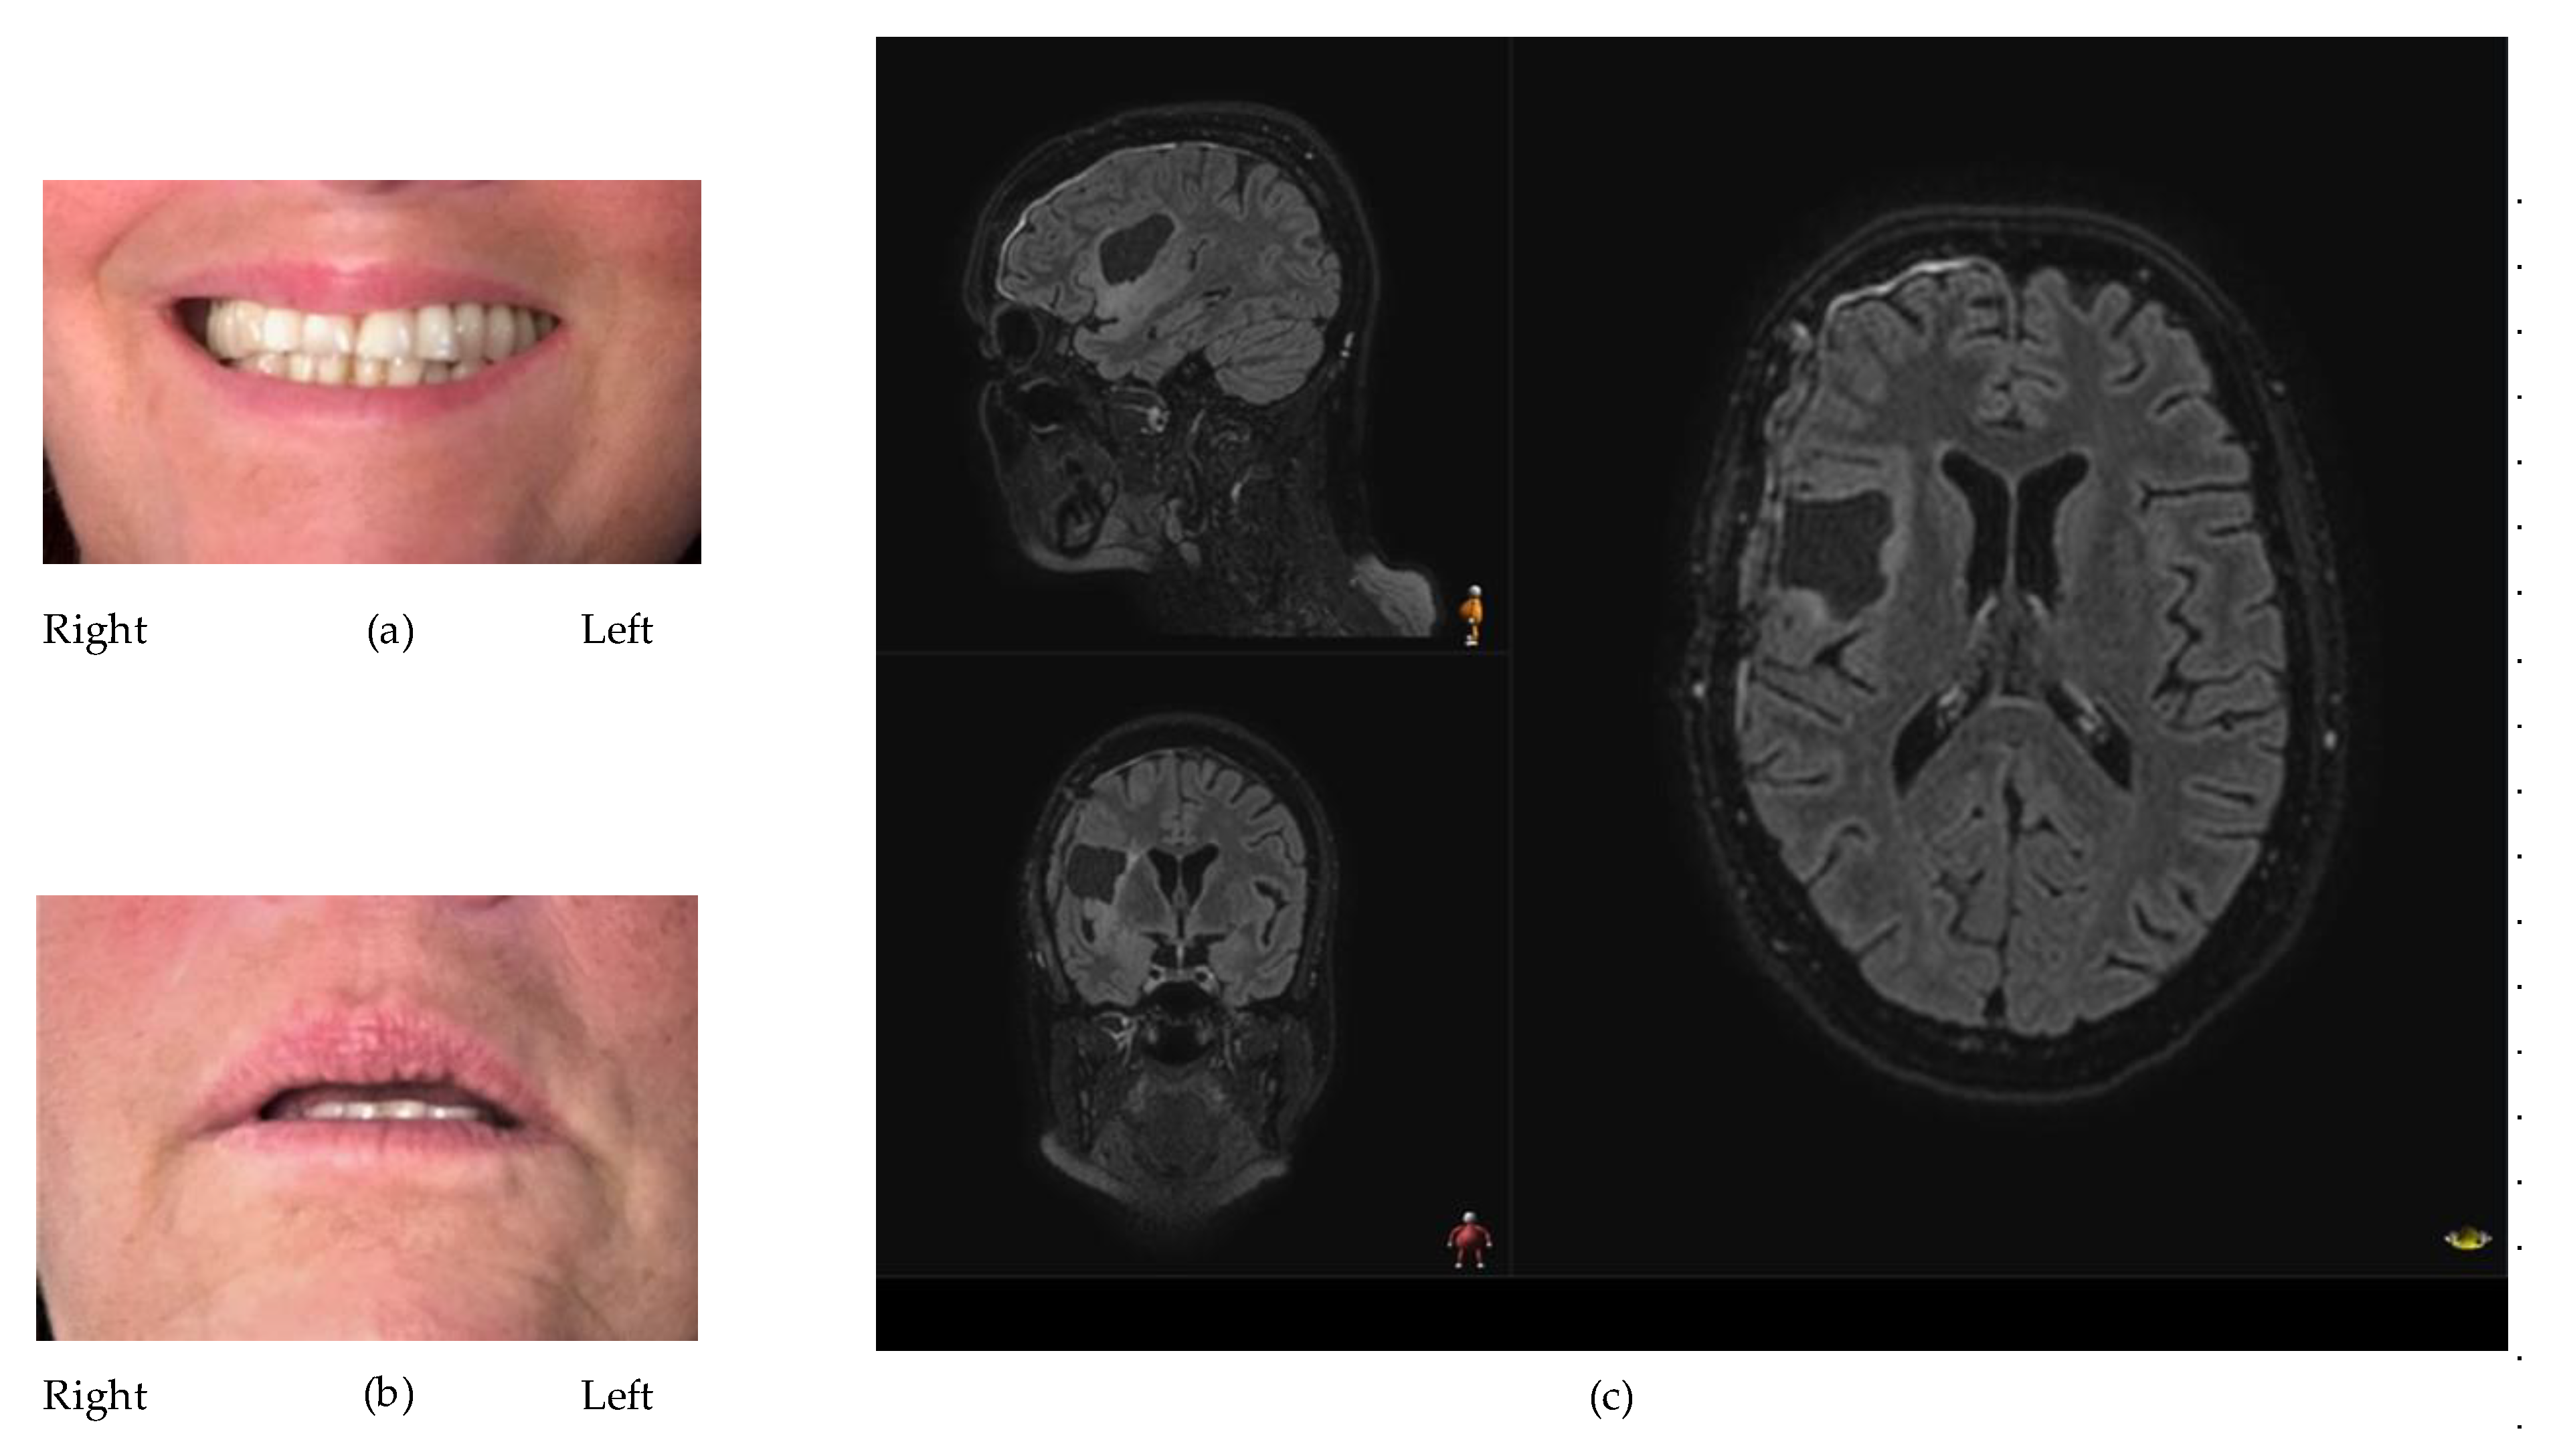

3.2. Facial Motor Function

Postoperatively, one patient was classified as normal regarding facial motor function according to the House–Brackmann scale (TN74). The remaining patients were classified as having mild dysfunction with slight asymmetries of the mouth (i.e., House–Brackmann score = 2). However, as demonstrated in Figure 1, the effects on the symmetry of the mouth in this group were very subtle.

In the FaCE questionnaire, the glioma group had a mean above 90 in all dimensions except oral function, where the score was 82.1 (Table 1). One patient (SA71) reported that both sides of the face were affected, and two patients reported that one side was affected (JD75, AW49). When compared with published normative data on patients with facial palsy, the patients in this study scored significantly better in all domains except oral function (Figure 2).

Figure 1. Both the photographs and the MR image (T2 Flair) depict the patient with the most severe facial motor deficit. (a) The patient has been instructed to show as big a smile as possible. A slightly less pronounced left furrow can be noticed. During the execution of the smile, the left side was slightly less responsive. (b) The patient was instructed to relax the face with a slight separation of the lips. A slight lowering of the left corner of the mouth can be noticed. (c) MR image (T2 Flair) of the resection cavity approximately 5 months postop.